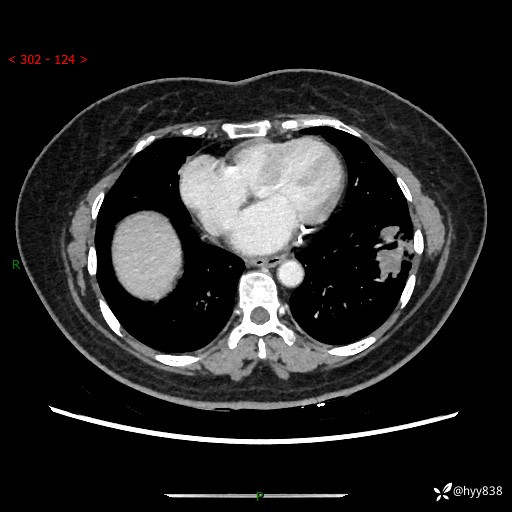

【现病史及既往史】:患者自诉2月前体检发现肺结节(左肺下叶约17mm,右肺上叶4mm),未予特殊处理,2024-10-12当地市第五医院门诊复查胸部CT提示右下肺结节(大小约3.3cm*3.9cm),患者无咳嗽、咳痰,无畏寒、发热、盗汗,无咯血,无胸闷、胸痛、呼吸困难,无恶心、呕吐,无腹痛、腹胀、腹泻等不适,现为求进一步诊治,门诊以“孤立性肺结节”收住我科。 患者本次起病来精神、食欲、睡眠尚可,大小便正常,体力、体重无明显变化。

【检查】:胸部CT增强检查